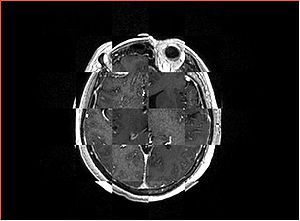

• Checkerboard appearance of unregistered images for the representative data of interest

• Case01